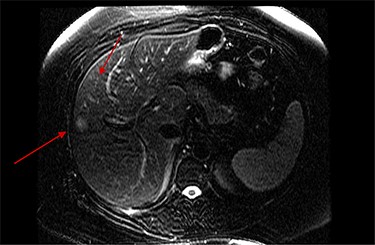

On assessment, the patient denied any symptoms related to her neuroendocrine tumor, including flushing, increased sweating, increased heart rate, wheezing, shortness of breath, diarrhea, weight loss or appetite changes. The only significant family history was a paternal and maternal grandfather with colon cancer. Imaging results were significant for computed tomography (CT) of chest demonstrating very small, but multiple, pulmonary nodules. A CT abdomen and pelvis demonstrated the known neuroendocrine tumor near the ileocecal valve (Fig. 1) as well as two poorly visualized liver lesions (Figs 2–4). The magnetic resonance imaging (MRI) demonstrated two separate one-centimeter lesions in segment 5 and 7 of the liver (Figs 5 and 6). The portal vein lacked normal left and right bifurcation; there was a circumferential right portal vein, which coursed anteriorly and superiorly and ultimately to the left lobe of the liver.

MRI image again demonstrating segment 5 metastatic lesion in close proximity to portal vein.